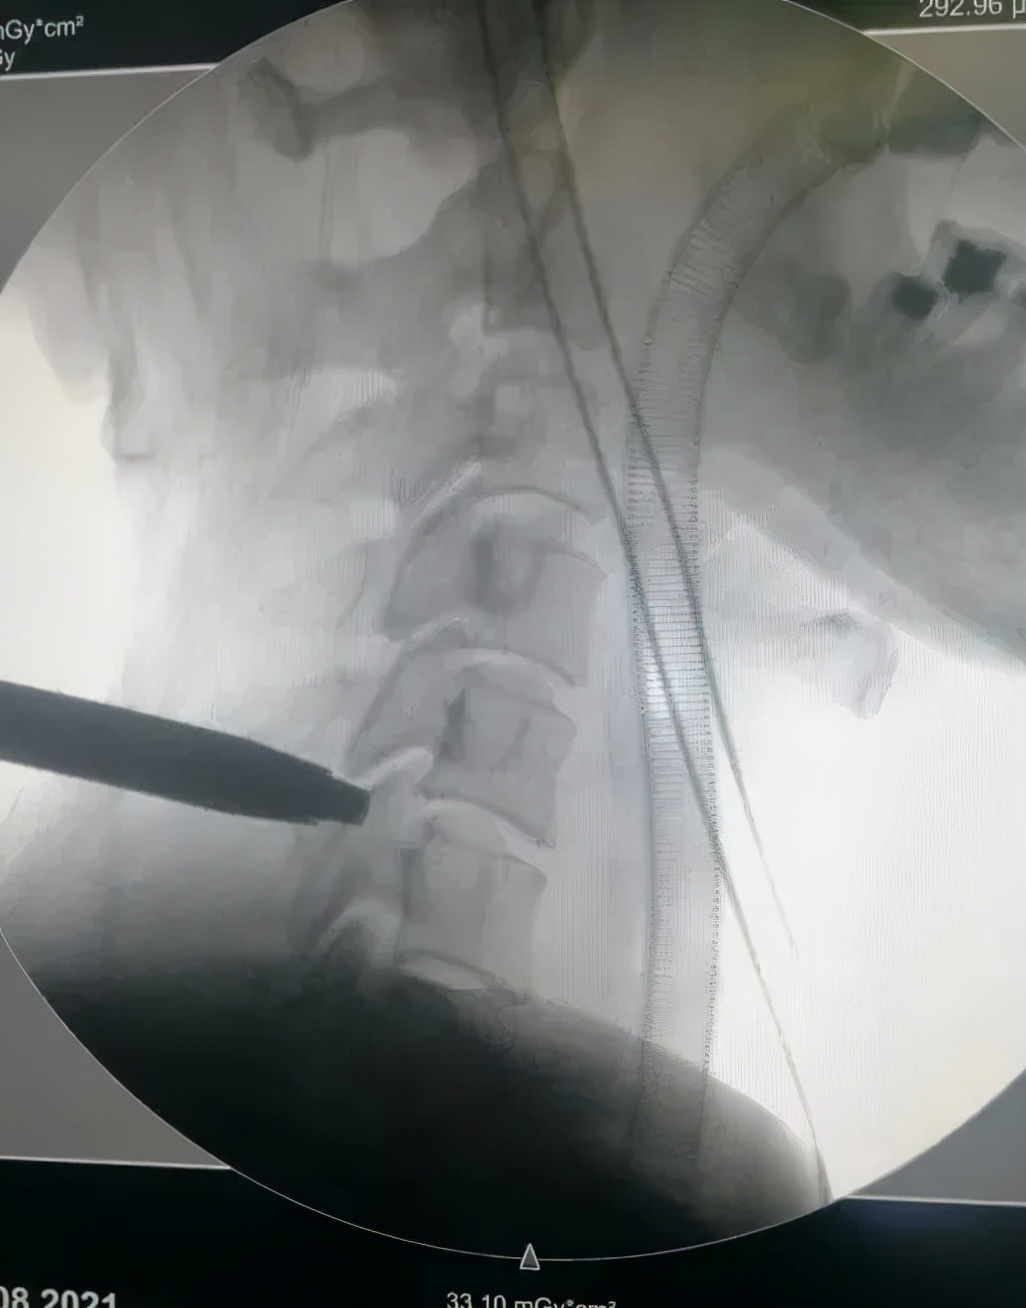

术中图示

经过脊柱关节外科中心会诊,诊断患者为神经根型颈椎病,根据患者的典型症状,医生建议行微创颈椎后路椎间孔切开术KEY-hole(钥匙孔技术)。在脊柱关节外科中心手术团队的共同努力下,手术过程顺利,术后患者恢复良好。